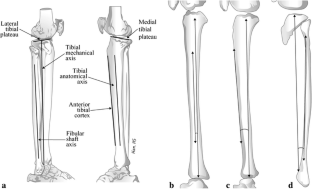

The authors aimed to demonstrate the relationship between the sagittal mechanical axis of the tibia and other reference axes of the tibia and fibula in patients with advanced osteoarthritis of the knee joints, and then to identify a reliable landmark in order to minimize posterior tibial slope measurement errors. We evaluated 133 osteoarthritic knees with neutral or varus deformity in 64 female and 8 male patients. Axial computed tomographic images of whole tibiae including knee and ankle joints were obtained and reconstructed using 3-dimensional imaging software. Angles between the mechanical axis (MA), the tibial anatomical axis (TAA), the anterior tibial cortex (ATC) and the fibular shaft axis (FSA) were measured, and then medial and lateral tibial slope angles were measured using all axes. Mean angles between MA and the other anatomical reference lines (TAA, ATC and FSA) were 0.9, 2.2 and −2.1°, respectively. The mean values of lateral tibial slopes with respect to MA, TAA, ATC and FSA were 8.7, 10, 12 and 7.3, respectively, and their intra- and inter-observer reliabilities were higher than those of medial tibial slopes. Although posterior tibial slope change markedly according to the reference axis used, the axes used in conventional TKA showed significant correlations with each other, and thus, may be used safely if differences with the mechanical axis are considered. Moreover, the lateral tibial slope might have advantages over the medial tibial slope in terms of restoration of the natural tibial slope.

Fig. 1